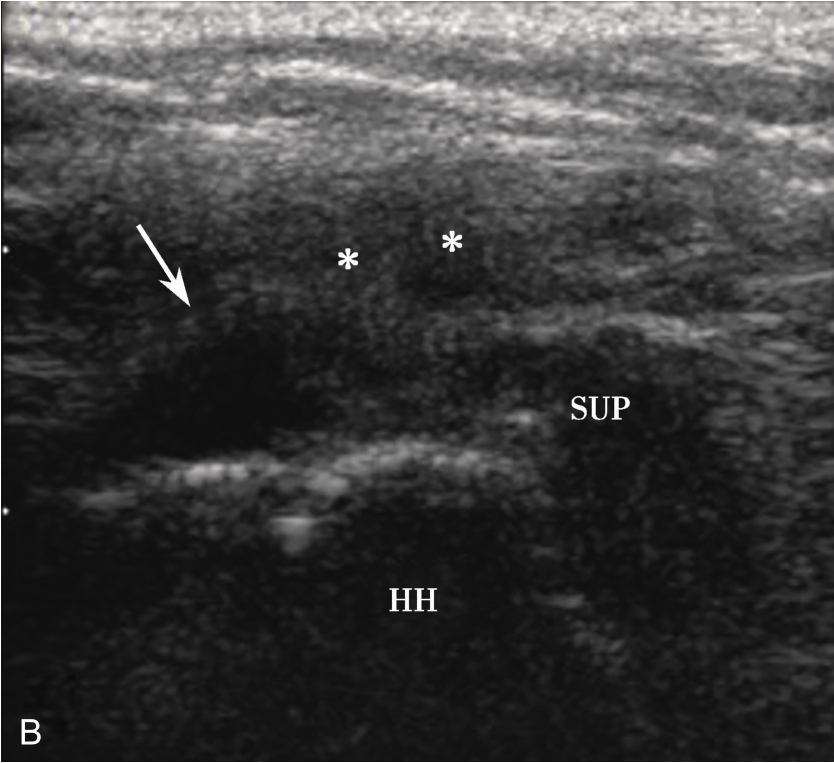

3.当肩袖回声不均匀,有可疑的滑囊面撕裂或全层撕裂,行超声引导下肩峰下-三角肌下滑囊造影检查,可提高对肩袖撕裂的诊断率。方法:将2~5ml生理盐水与0.5ml的超声造影剂混合后,注入肩峰下-三角肌下滑囊,无撕裂的滑囊呈线状高增强(图2-1-8),肩袖滑囊面部分撕裂可见造影剂混合液从滑囊进入肩袖肌腱内而未达肱骨头表面(图2-1-9),若观察到其进入肩关节腔或肱二头肌长头腱鞘,则诊断肩袖全层撕裂(图2-1-10)。

▲ 图2-1-9 超声引导下肩峰下-三角肌下滑囊造影图(二)

A.超声引导下滑囊内注入超声造影剂后,滑囊呈线状高增强,肌腱内可见局限性高增强,提示肌腱滑囊面部分撕裂(箭头);B.二维超声显示冈上肌腱(SUP)回声不均匀(箭头),但未见明显撕裂,HH:肱骨头